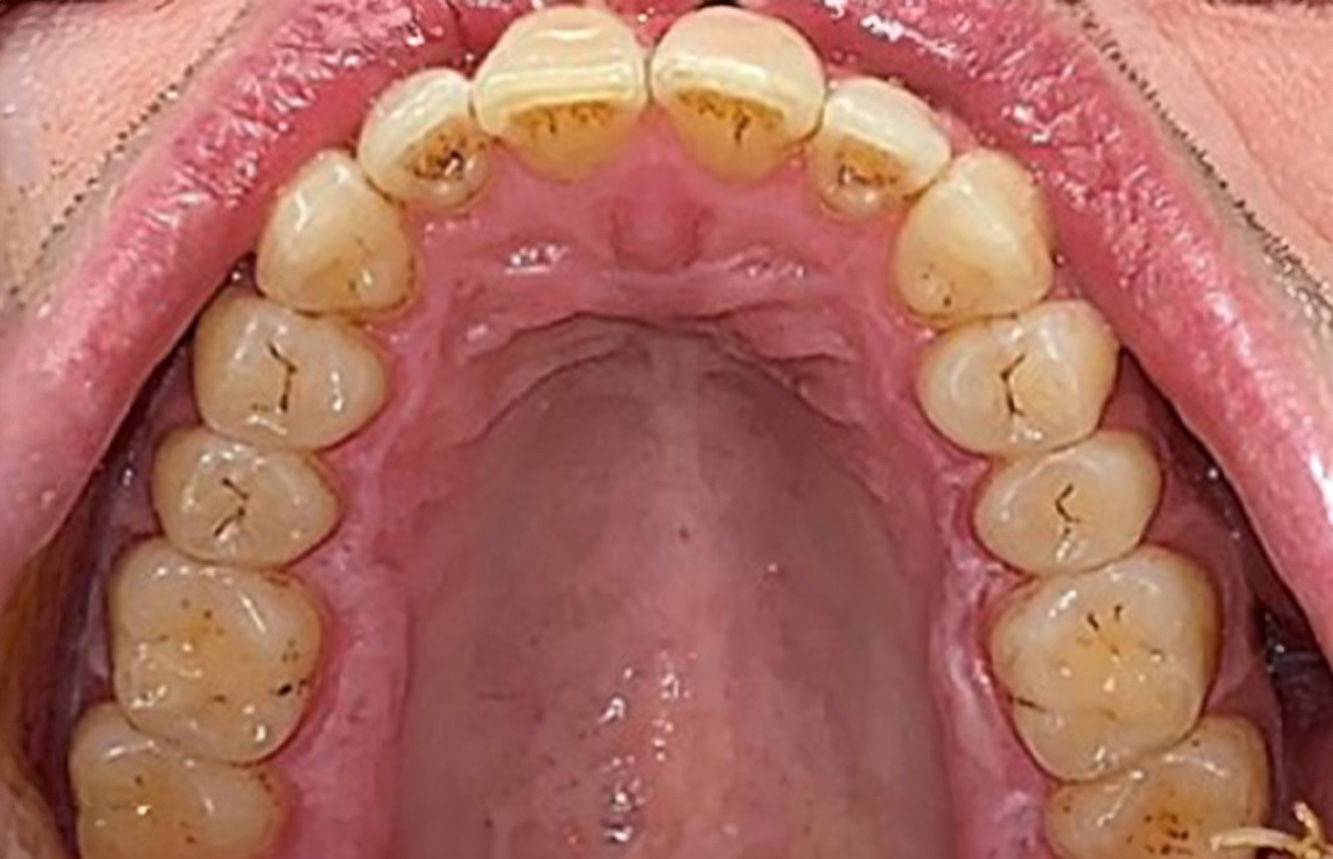

Der gesunde Patient mit parodontaler Vorerkrankung & Periimplantitis

Ein 52-jähriger Patient stellt sich zur Präventionssitzung vor. Der Patient hat keine Allgemeinerkrankungen und nimmt keine Medikamente ein. Er hat verschiedene zahnärztliche Versorgungen und zudem zwei aktive kariöse Läsionen. Außerdem verfügt der Patient über vier Implantate (2., 3. und 4. Quadrant). Es zeigt sich eine parodontale Vorerkrankung (Stadium IV, Grad B). Derzeit herrschen stabile parodontale Verhältnisse, lediglich am Implantat regio 36 zeigen sich Sondierungstiefen (ST) von 5 mm. Zudem lässt sich eine Gingivitis feststellen. mehr Infos